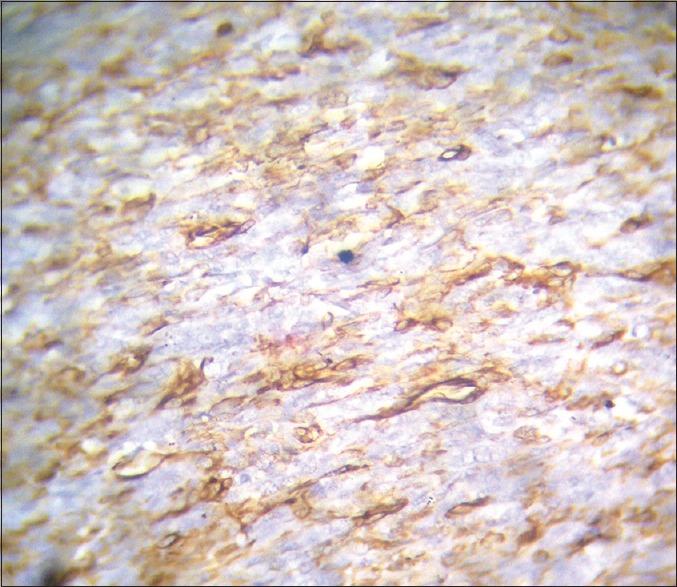

Fibrosarcoma is a malignant tumor of fibroblasts. At one time, it was considered one of the most common soft tissue sarcomas. However, the diagnosis of fibrosarcoma is made much less frequently today because of the recognition and separate classification of other spindle cell lesions that have similar microscopic features. Of all the fibrosarcomas occurring in humans, only 0.05% occur in the head and neck region. Here, we present a case of 22-year-old female patient with the swelling on the left anterior aspect of the face. Histopathologically, the lesion was diagnosed as fibrosarcoma and immunohistochemically, the lesional cells showed positivity for vimentin.

纤维肉瘤是成纤维细胞的恶性肿瘤。曾有一段时间,它被认为是最常见的软组织肉瘤之一。然而,如今纤维肉瘤的诊断频率大大降低,因为其他具有相似微观特征的梭形细胞病变得到了认识并被单独分类。在所有发生于人类的纤维肉瘤中,仅有0.05%发生于头颈部区域。在此,我们报告一例22岁女性患者,其面部左侧前位出现肿胀。组织病理学上,该病变被诊断为纤维肉瘤,免疫组织化学检查显示病变细胞波形蛋白呈阳性。